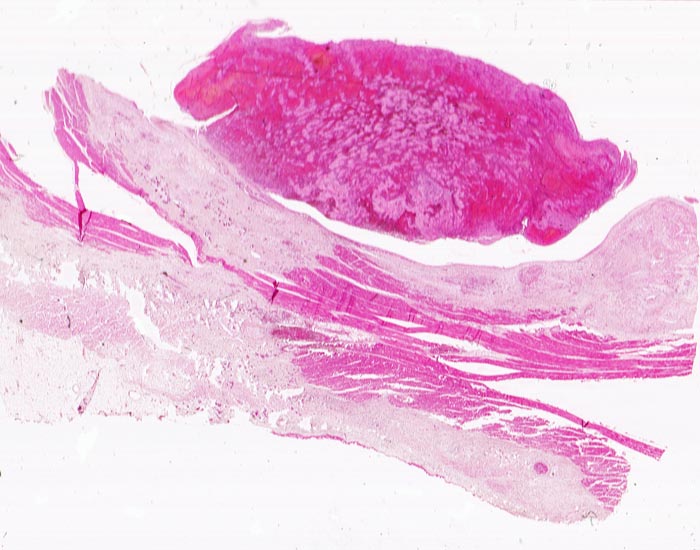

PathoPic ID 4567 - Transmuraler Myokardinfarkt mit Parietalthrombose

Transmuraler Myokardinfarkt mit Parietalthrombose

vaskulär / Durchblutungsstörung

Herz links

Kardiovaskuläres System

Hypereosinophiles nekrotisches

Myokard. Dem Endokard zum Ventrikellumen hin anhaftender geschichteter Thrombus. Dünne

Fibrinschicht auf dem Epikard.

Diagnose eines Myokardinfarktes vor 4 Tagen.